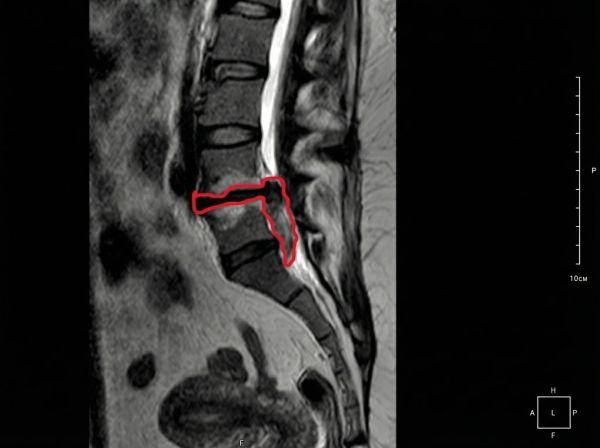

Пациентка, 45 лет. Грыжа секвестрированная, 3.5 сантиметра.

Грыжи нет, остался только рубец.